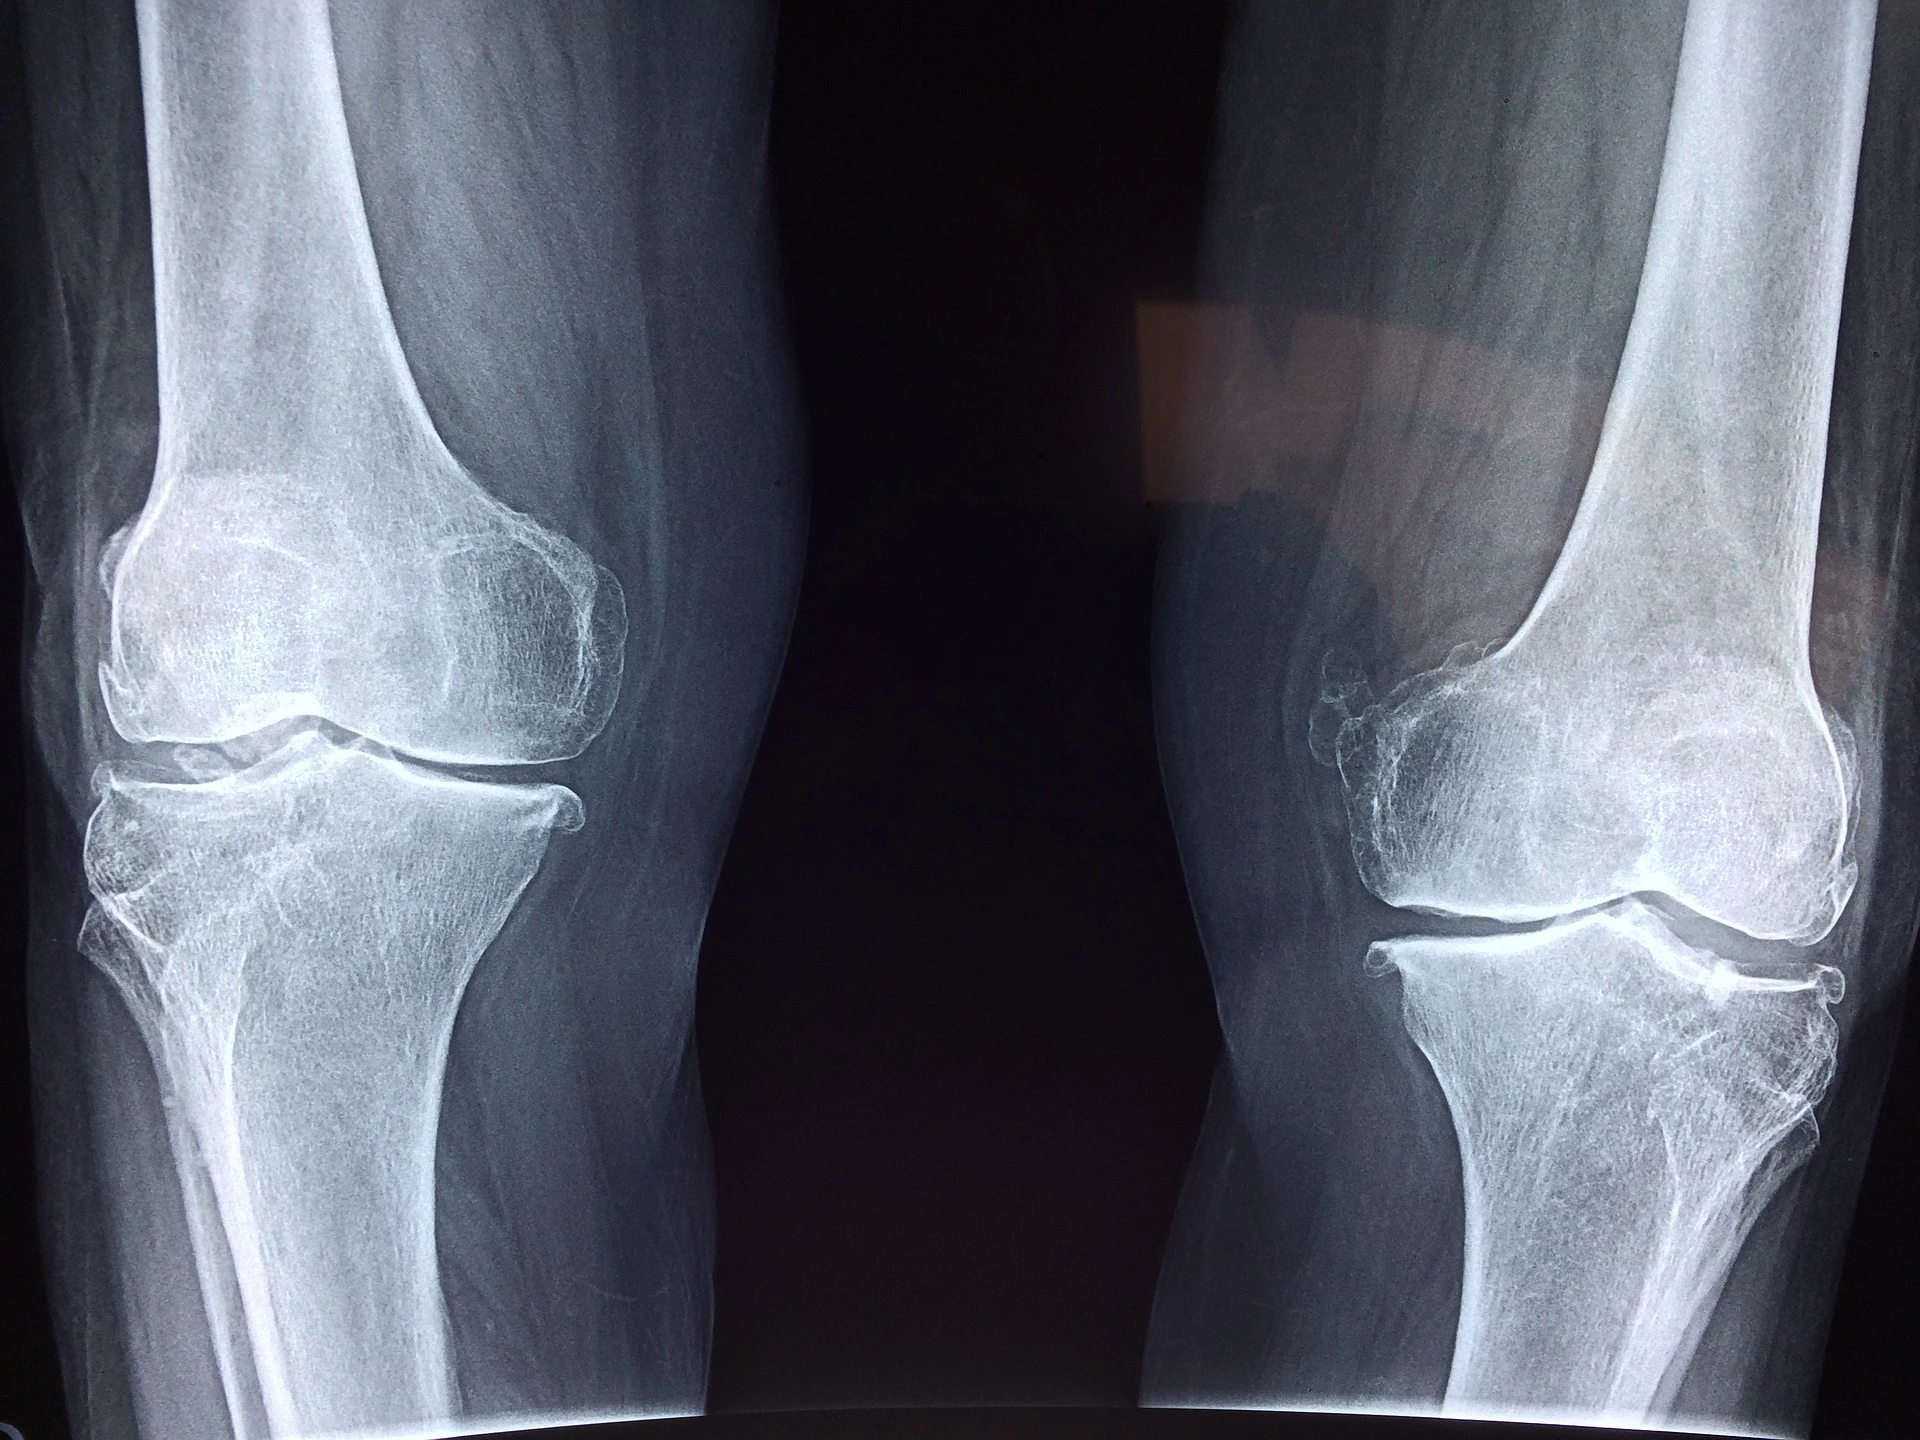

As an OB/GYN, osteoporosis is generally a topic of conversation I address with patients who are approaching or past menopause. Osteoporosis is a condition that weakens the bones and causes them to break easily. Although anyone can develop osteoporosis, women past menopause are at the highest risk. But that doesn’t mean you should wait to worry about your bone health. There are predetermining factors to be aware of and some steps you can take to ensure healthy bones in the future.

So, how do you know if you have osteoporosis? Truthfully, it’s difficult to know. Most patients with osteoporosis do not present any symptoms until after they have a fracture. The most common fracture occurs in the vertebrae, which is typically identified on a chest X-ray that is often done for another reason (like examining lung function).

If you’re concerned or wondering about your bone health, there are a couple of options. Ask your doctor when it would be appropriate to start screening for osteoporosis. Discuss any medical or family history that specifically concerns you. Your doctor should be able to tell you some ways to improve your bone health and decrease your risk of osteoporosis. You can also schedule a bone density screening. Baylor Scott & White Health has 11 Women’s Imaging Centers that offer bone density screenings, which can help determine if you currently have osteoporosis or can help calculate your risk of breaking bones. Sometimes this screening can be included in annual well-woman exams for age 50 and above.